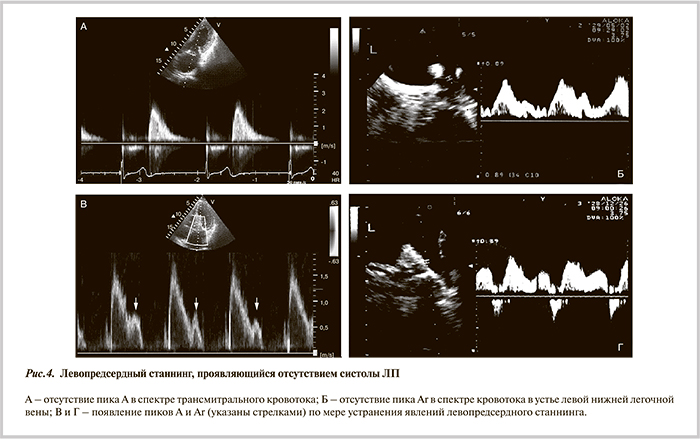

В 4 случаях индуцировалось ТП или наблюдалась интраоперационная конверсия ФП в ТП. Путем электроанатомического картирования и вхождения в цикл тахикардии во всех случаях подтвердился механизм перимитрального re-entry или re-entry вокруг попарно изолированных ЛВ. В этом случае создавали дополнительные линейные повреждения по крыше ЛП и от правой верхней ЛВ к кольцу МК (рис. 3, см. цв. вклейку). Восстановление СР непосредственно во время процедуры произошло у 6 из 10 пациентов. На фоне ААТ через 6 мес у всех пациентов регистрировался СР, по данным ЭКГ и трехсуточного мониторирования ЭКГ. В первые дни после катетерной процедуры у большинства пациентов регистрировались явления оглушения («станнинга») ЛП, что проявлялось отсутствием предсердной систолы в спектре трансмитрального кровотока. В динамике отмечалось восстановление сократительной функции ЛП: через 1 мес у 4 пациентов, через 3 и 6 мес — у 6 и 8 соответственно, через 1 год у всех пациентов регистрировалась эффективная систола ЛП со средней скоростью волны А трансмитрального кровотока 0,68±0,11 м/с (рис. 4). Это позволило отменить варфарин пациентам с протезированными биологическими клапанами сердца и снизить уровень гипокоагуляции до нижней границы целевого диапазона при механических протезах.

Необходимо подчеркнуть важность сохранения механической функции ЛП, страдающей у пациентов после процедуры «Лабиринт» из-за большого объема повреждаемого предсердного миокарда. В нашей серии вмешательств непосредственно после выполнения катетерной РЧА во всех случаях регистрировались явления левопредсердного станнинга. Однако в отдаленные сроки более чем у 50% пациентов наблюдалась адекватная сократимость ЛП при сохранении СР, что позволило отменить варфарин. Данные ЭхоКГ подкреплялись отсутствием клинической симптоматики и данными трехсуточного мониторирования ЭКГ.